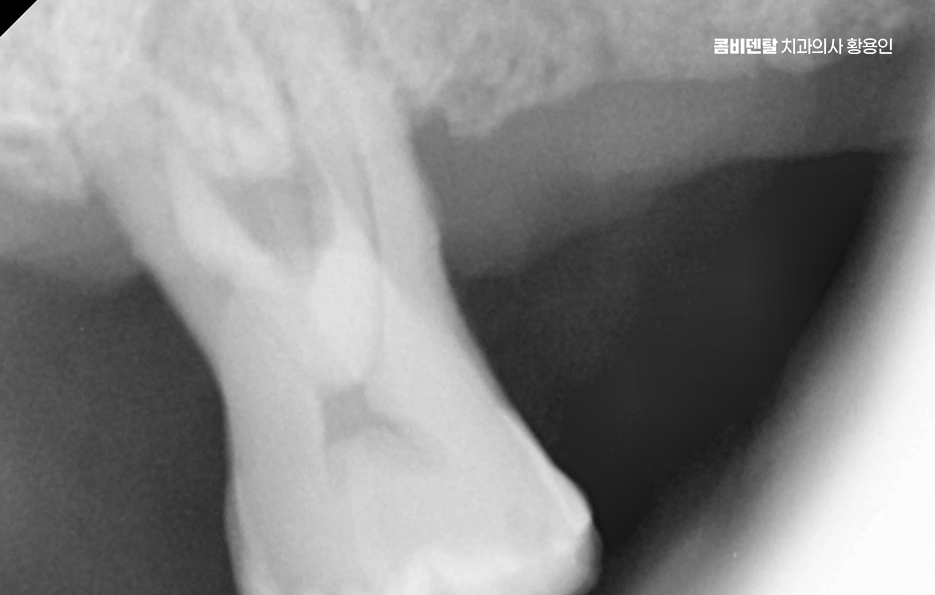

보통 윗니 전체 임플란트를 계획할 때 먼저 해야 하는 건 CT 촬영을 통한 잇몸 뼈 상태 진단으로 윗니는 아래보다 뼈가 더 얇고, 특히 어금니 쪽에는 상악동이라는 빈 공간이 있기 때문에, 임플란트를 심을 수 있는 잇몸 뼈의 양이 부족한 경우가 많다보니 이런 경우에는 단순히 임플란트를 심을 수 없기 때문에 상악동 거상술이라는 수술이 필요하게 되는 경우도 있는데요

이 수술은 상악동 점막을 들어 올리고 그 아래에 뼈이식 재료를 넣어서 임플란트가 들어갈 수 있는 충분한 공간을 만들어주는 방식이며 그 외에도 잇몸 뼈 상태나 전신 건강, 흡연 여부 같은 조건에 따라 구체적인 치료 방법이 달라지기 때문에 이처럼 윗니 전체 임플란트의 경우 기본적으로 임플란트를 지지할 수 있는 잇몸 뼈가 충분한지 정확한 진단이 치료의 시작점이 되고 있어요